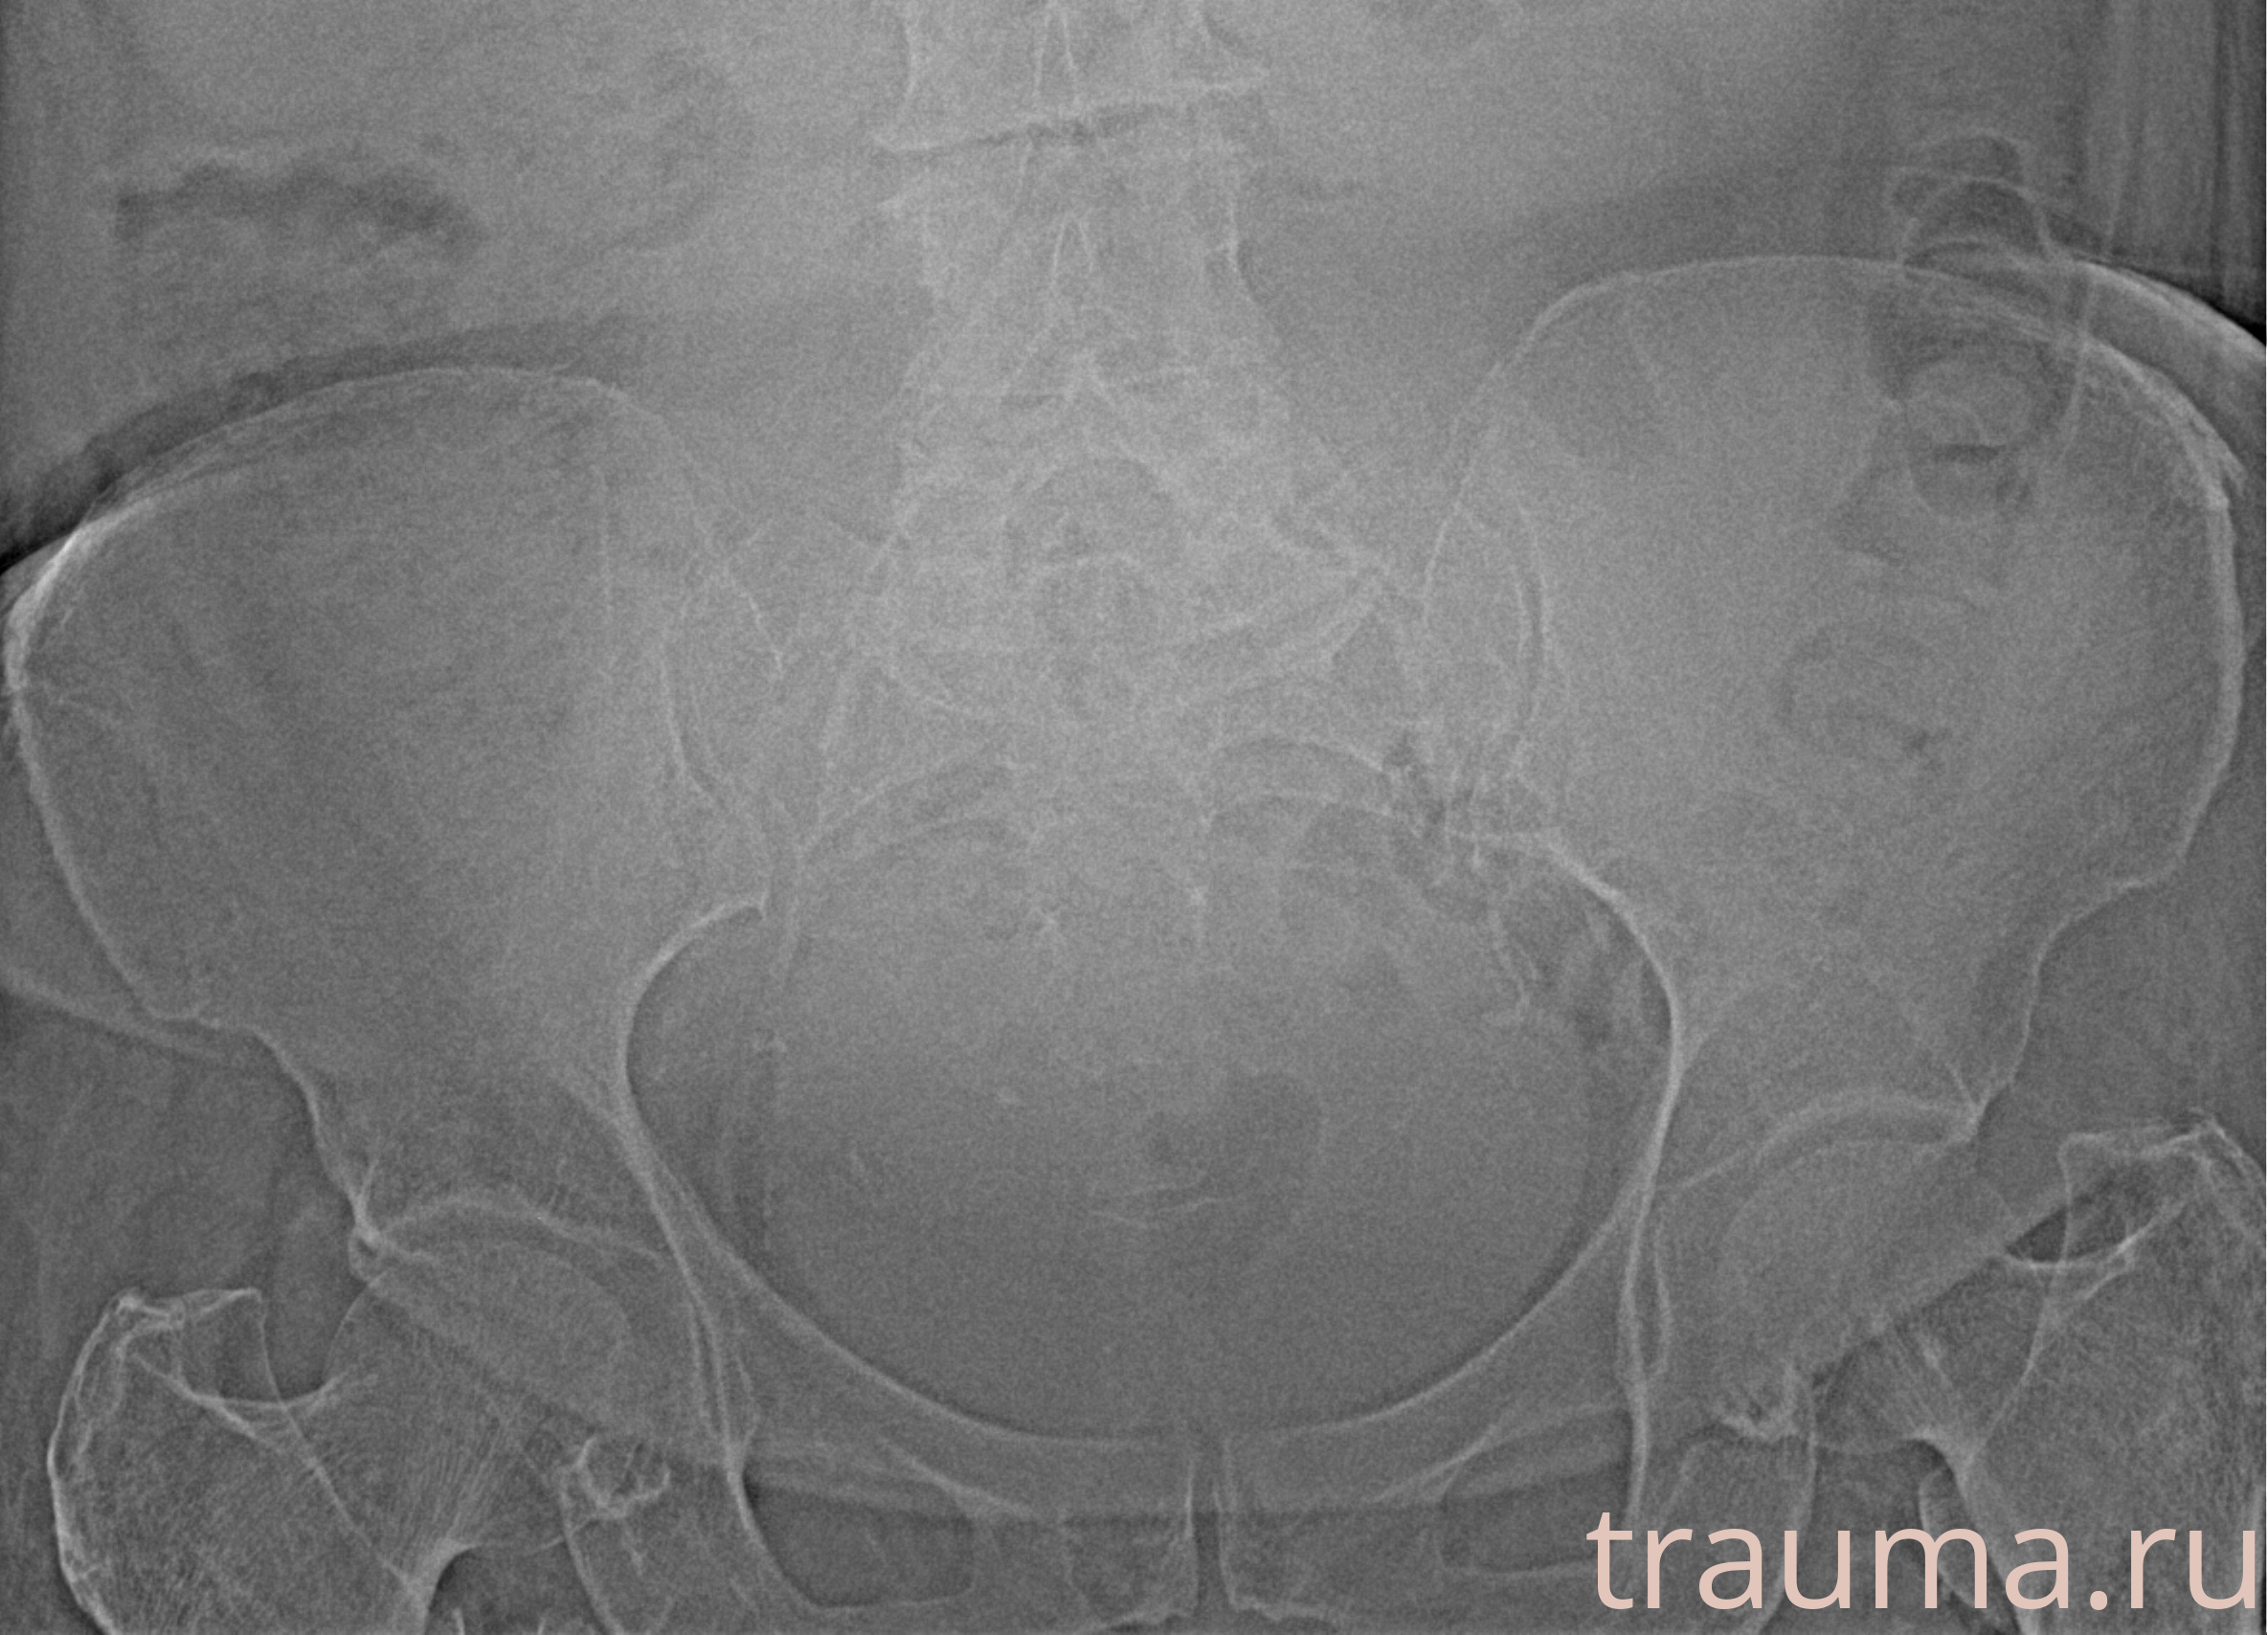

Рентгенограммы

Рентген на дому: по вашему адресу приезжает врач-рентгенолог, травматолог-ортопед с мобильным рентгеновским аппаратом, проводит диагностику травмы или заболевания, делает необходимые рентгенограммы, дает рекомендации по дальнейшему лечению. Получить качественные снимки в домашних условиях возможно благодаря уникальной методике, разработанной МосРентген Центром для института  Склифосовского